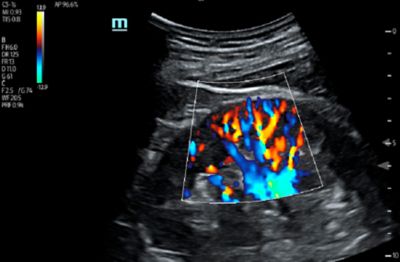

• High-sensitivity Doppler modes

• Contrast Enhanced Ultrasound (CEUS)